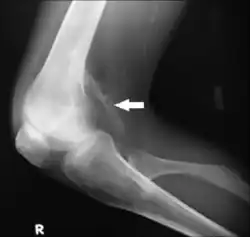

Calcification of muscle can occur after traumatic injury and is known as myositis ossificans. It can be recognized by muscle tenderness and loss of stretch in the affected area. To reduce the risk of calcification after an injury, initiate what is commonly known as "RICE" (rest, ice, compression, and elevation).[2]

Typically, the diagnosis of extra-skeletal ectopic calcification is quite straightforward. A physical examination of a suspected area with calcified deposits palpates as hard and rough. To confirm, the calcified tissues can be seen on an x-ray.